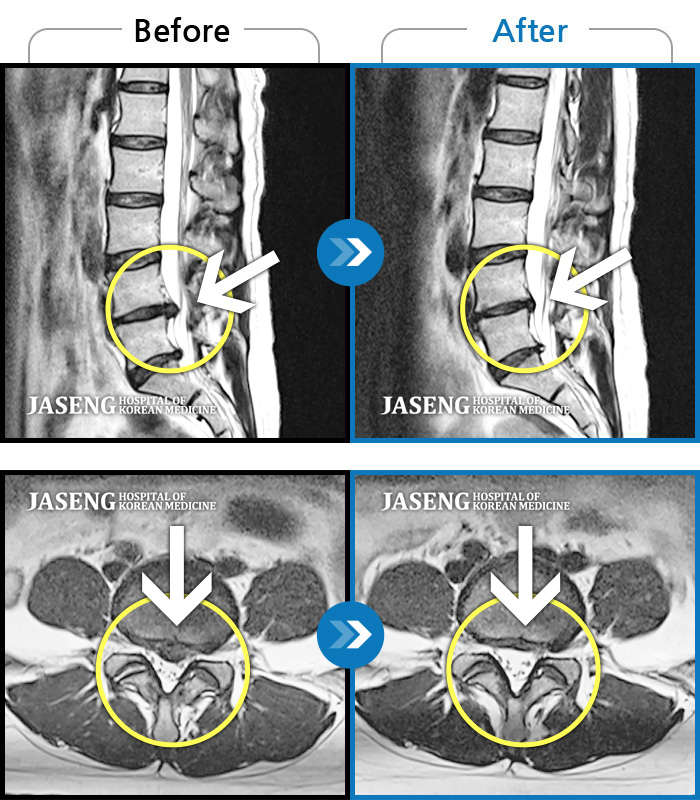

MRI 치료사례

허리 중간부위 통증, 간헐적으로 양측 엉치 부위 저림